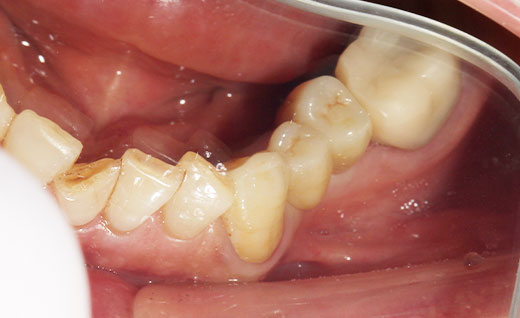

施術中

ジルコニアブリッジの土台を形成しているところです。